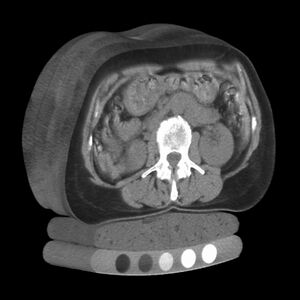

Tomography is imaging by sections or sectioning that uses any kind of penetrating wave. The method is used in radiology, archaeology, biology, atmospheric science, geophysics, oceanography, plasma physics, materials science, cosmochemistry, astrophysics, quantum information, and other areas of science. The word tomography is derived from Ancient Greek τόμος tomos, "slice, section" and γράφω graphō, "to write" or, in this context as well, "to describe." A device used in tomography is called a tomograph, while the image produced is a tomogram.

In many cases, the production of these images is based on the mathematical procedure tomographic reconstruction, such as X-ray computed tomography technically being produced from multiple projectional radiographs. Many different reconstruction algorithms exist. Most algorithms fall into one of two categories: filtered back projection (FBP) and iterative reconstruction (IR). These procedures give inexact results: they represent a compromise between accuracy and computation time required. FBP demands fewer computational resources, while IR generally produces fewer artifacts (errors in the reconstruction) at a higher computing cost.[1]